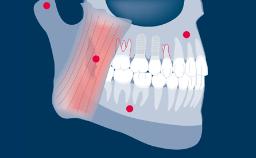

Prosthodontic Planning Principles for Implant Placement

Regardless of the location or extent of treatment, the planning of implant therapy should always be prosthodontically driven.

This ensures that the implant placement will serve the needs of the prostheses and will be compatible with the desired end result.

With the aim of achieving an optimal outcome, the prosthodontic planning should include consideration of all relevant prosthodontic factors and an appropriate diagnostic work-up as the basis for the specific planning of implant prostheses and supporting implants.

- discuss general prosthodontic planning considerations related to implant therapy

- explain the benefits of a diagnostic prosthodontic work-up for implant placement

- outline the specific planning points for implant prostheses and their supporting implants